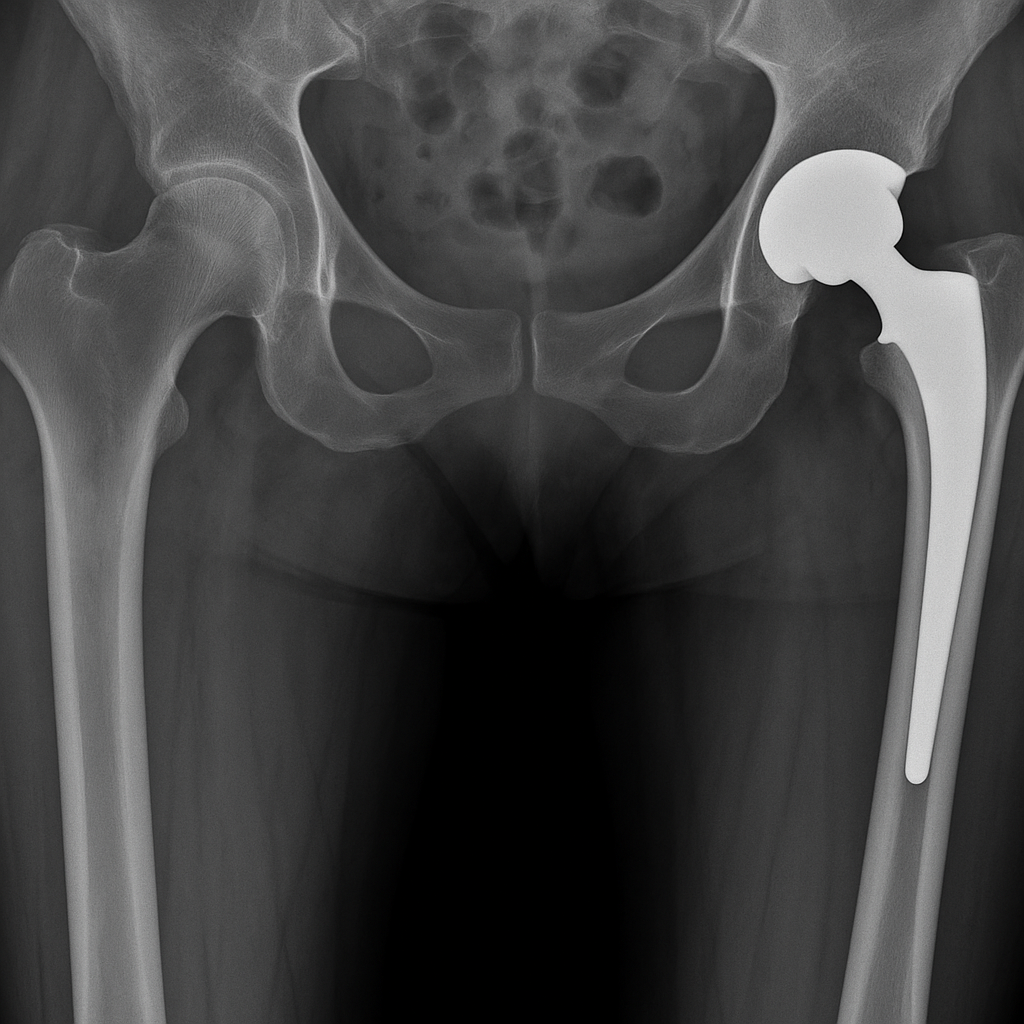

Quand référer un patient pour une prothèse de hanche ?

Comprendre la pathologie de la hanche La hanche est une articulation essentielle à la mobilité, souvent sollicitée au quotidien. Lorsque cette articulation se détériore à cause de l’arthrose, d’un traumatisme ou de certaines maladies inflammatoires, la douleur peut devenir invalidante. Les traitements médicaux et la rééducation permettent dans un premier temps de soulager les symptômes, … Read more